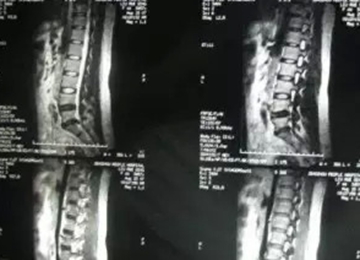

核磁矢状位

2007年,刘女士,43岁,L5-S1椎间盘脱出0.8cm,胶州市人民医院外聘专家要求手术。不能行走,夜间痛性,主要表现为腿后侧。